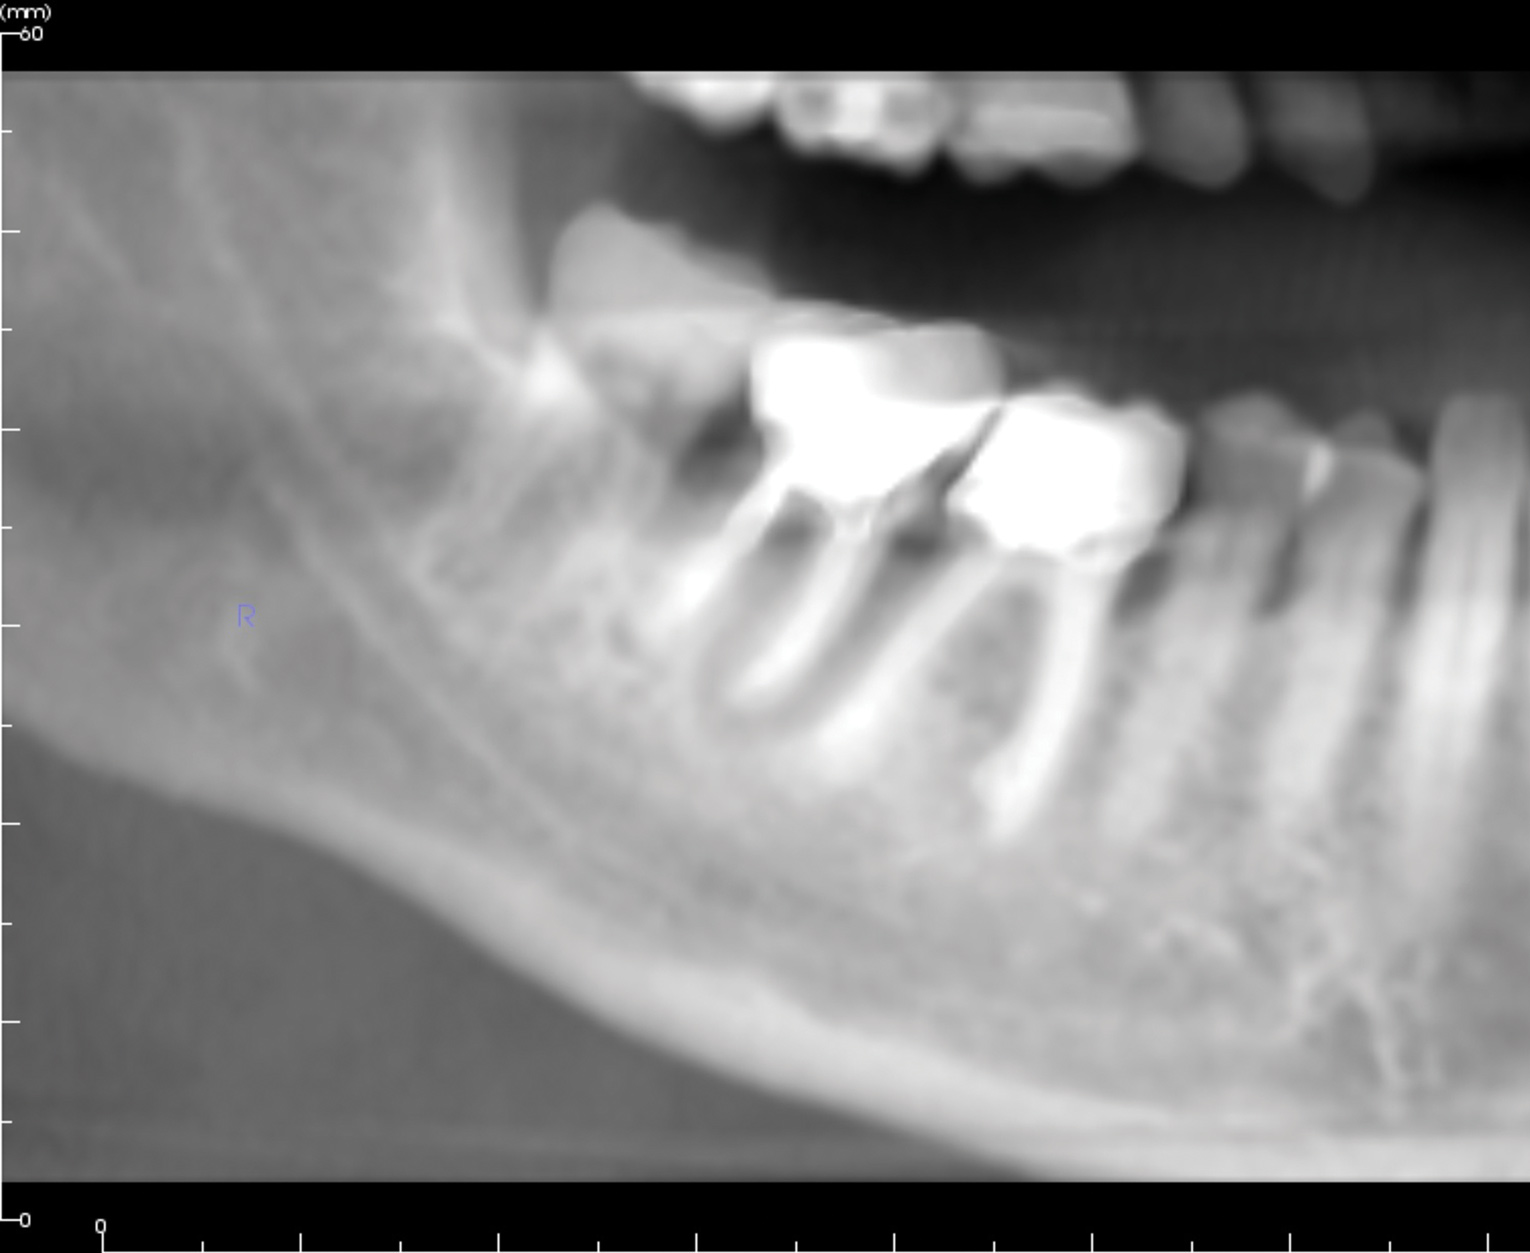

A 70-year-old female patient displayed a fractured root at the maxillary left lateral incisor and was requesting immediate implant reconstruction (Figure 1 and Figure 2). The patient's medical history was significant for appropriate medical management of gastroesophageal reflux disease (GERD), hypothyroid, osteoarthritis, anemia, and history of skin cancer. Clinical evaluation and cone-beam computed tomography (CBCT) assessment (with a dynamic navigation fiducial) facilitated planning with evaluation of labial undercut, buccal bone dimensions, 3-dimensional (3D) implant positioning, and retention screw access path (Figure 3).

Fig 1. Occlusal view of maxillary left lateral incisor.

Figure 1